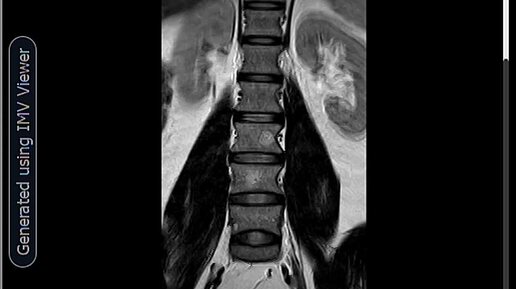

МРТ-Гемангиома тела L3 позвонка, очаг жировой дегенерации L4